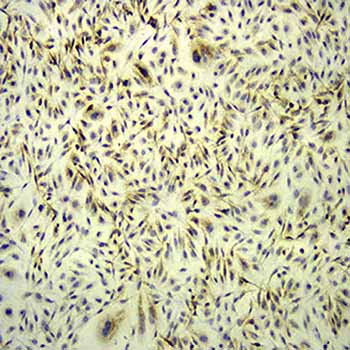

免疫组织化学又称免疫细胞化学,可以用于:(1)显色剂标记的特异性抗体在组织细胞原位通过抗原抗体反应和组织化学的呈色反应;(2)是对相应抗原进行定性、定位、定量测定的一项新技术。

免疫组织化学又称免疫细胞化学,是指带显色剂标记的特异性抗体在组织细胞原位通过抗原抗体反应和组织化学的呈色反应,对相应炕原进行定性、定位、定量测定的一项新技术。

它把免疫反应的特异性、组织化学的可见性巧妙地结合起来,借助显微镜( 包括荧光显微镜、电子显微镜) 的显像和放大作用,在细胞、亚细胞水平检测各种抗原物质( 如蛋白质、多肽、酶、激素、病原体以及受体等) 。

二,免疫组化技术的基本原理

免疫组化技术是一种综合定性、定位和定量;形态、机能和代谢密切结合为一体的研究和检测技术。在原位检测出病原的同时,还能观察到组织病变与该病原的关系,确认受染细胞类型,从而有助于了解疾病的发病机理和病理过程。

免疫酶组化技术是通过共价键将酶连接在抗体上,制成酶标抗体,再借酶对底物的特异催化作用,生成有色的不溶性产物或具有一定电子密度的颗粒,于普通显微镜或电镜下进行细胞表面及细胞内各种抗原成分的定位。